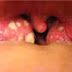

Penyakit amandel merupakan penyakit disebabkan oleh kelenjar tonsil atau basil nanah bercampur dengan basil fusifomis dan basil spirila. Penyakit amandel biasa menyerang anak di bawah usia limabelas tahun. Penderita penyakit amandel akan merasakan sakit pada tenggorokan, khususnya pada waktu menelan makanan. Terlebih lagi bila penderita

sakit amandel juga mengalami

batuk pilek, maka amandel biasanya akan semakin besar serta sangat sulit menelan makanan. Hal ini akan semakin lebih parah jika penderita mengkonsumsi es. Selain itu penderita sakit amandel akan mengalami